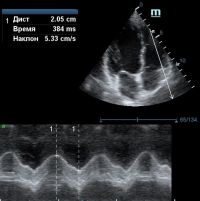

Но как же провести стандартные измерения в М-режиме, если мы его не использовали? На помощь приходит функция Free Xros M – анатомический М-режим. Имея записанную в память прибора видео петлю, мы можем провести линию М-режима в любом месте, при этом корректируя изначально не оптимальный угол.

TAPSE - показатель амплитуды движения латеральной части кольца трикуспидального клапана, позволяет количественно и быстро оценить систолическую функцию правого желудочка, норма которого составляет более 17 мм. Главным условием является проведение линии М-режима параллельно стенке правого желудочка в апикальном четырех камерном сечении, что легко достигается при Free Xros.